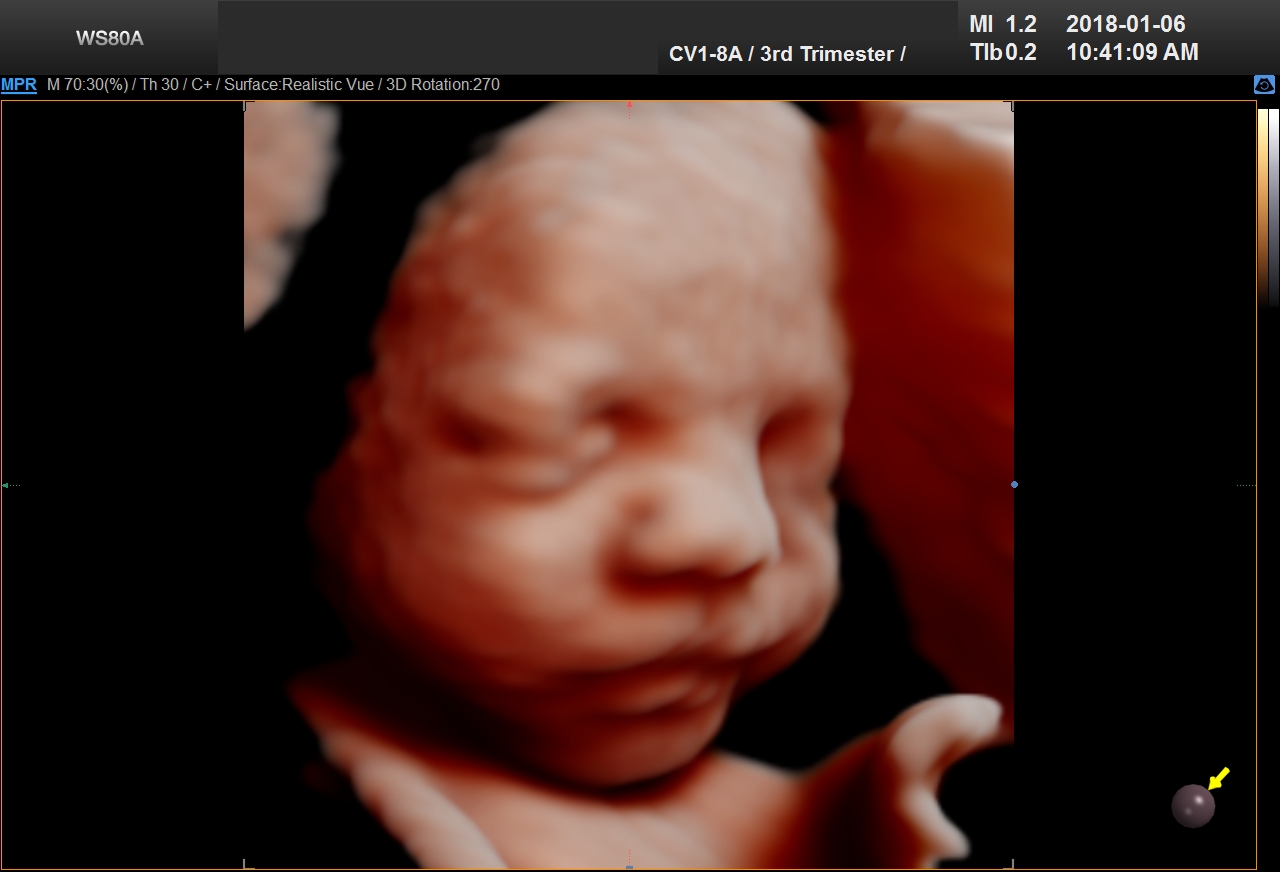

5D Ultrasound

5D Ultrasound is the newest development in pregnancy imaging and it is patented by Samsung. It captures and combines high definition volume data to create automated images with amazing color and clarity. The bond between a new baby and the family gets even stronger when the family can view realistic pictures of baby in a 5D ultrasound.

UC Baby’s Latest 5D Ultrasound Service Offering

UC Baby Calgary is the first facility which brought cutting edge 5D technology to Canada. This cutting edge new ultrasound machine provides realistic pictures of the baby using the most advanced features of ultrasound imaging. We are offering high-definition 5D ultrasound technology to create unforgettable memories without extra cost. This new ultrasound technology allows families to bond stronger to the baby, with clear views of baby’s face and movements. With 5D technology, it is even possible to notice the dimples when baby smiles!

The best time to have a 5D ultrasound is between 24-32 weeks of pregnancy. Our experienced and professionally trained staff are there to amaze the mothers and their families. We also offer free online accounts for captured 2D, 3D, 4D and 5D images / videos in addition to free live broadcast of the whole ultrasound session. This is the fastest and easiest way to share baby’s first pictures and videos with friends and family instantly.